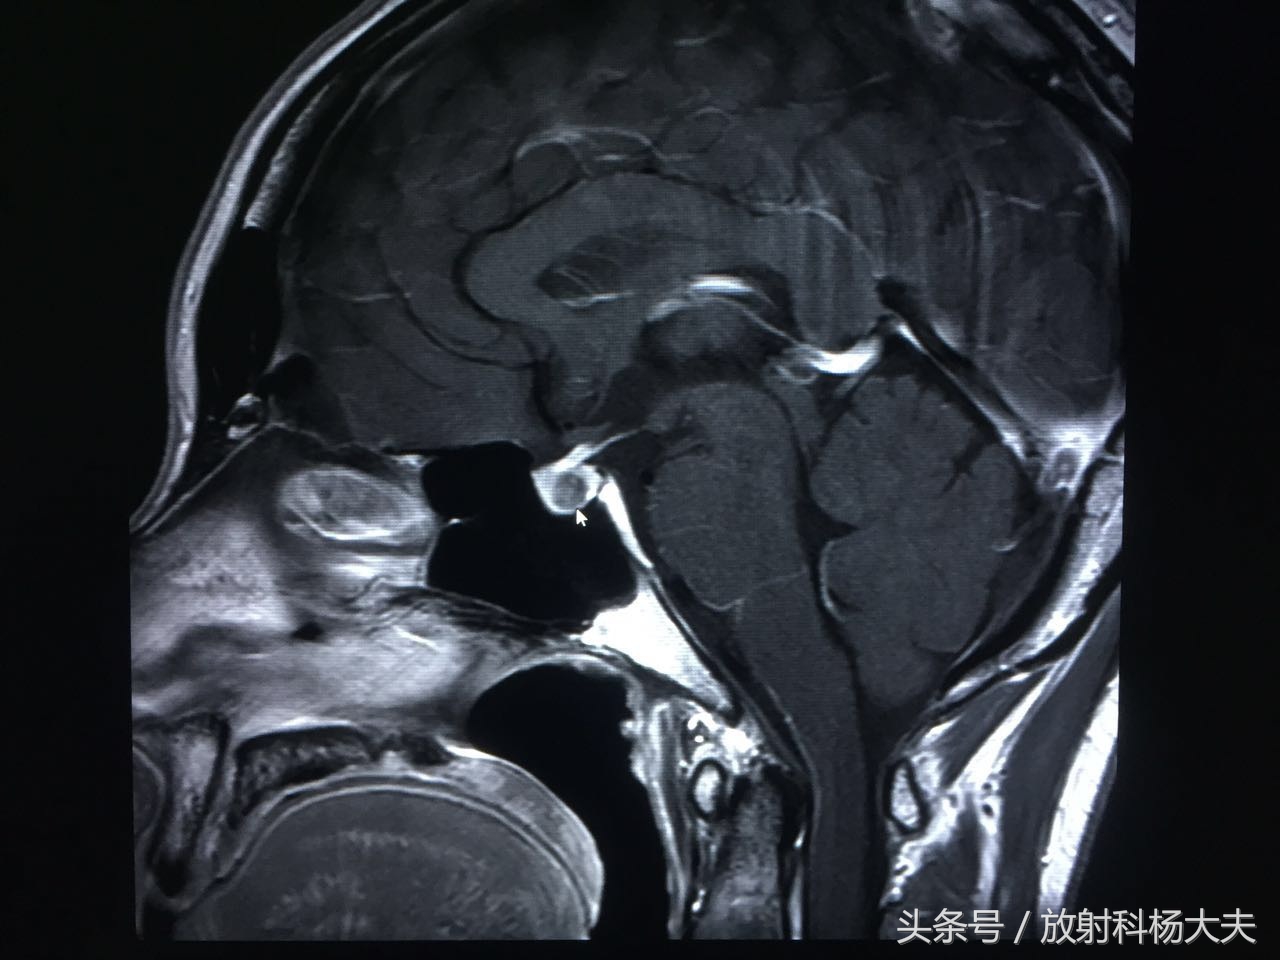

图像出来了,我们可看到垂体内的异常信号(短箭头所指地方),呈长T1混杂T2信号。

动态增强扫描可见延迟强化,其延迟期扫描强化程度仍低于周围正常腺体。余垂体强化均匀。

箭头所示的为垂体的瘤子